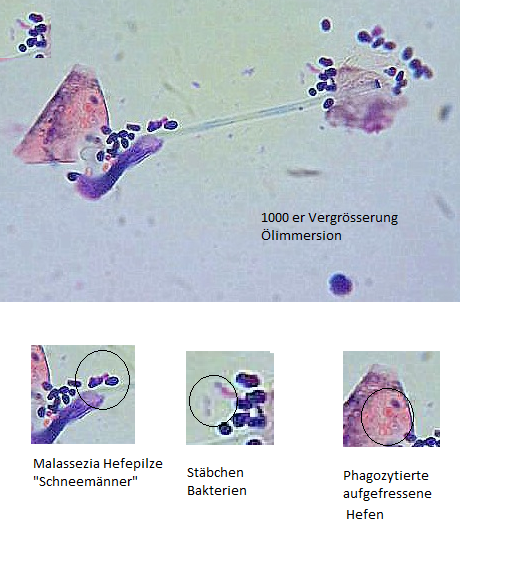

Eine ganz wichtige Untersuchung ist die Zytologie. Man rollt einen Wattetupfer auf einem Objektträger aus und färbt ihn an. Nun kann man erkennen, ob im Ohr ein Pilzproblem oder ein Befall mit Stäbchenbakterien oder Kokken vorliegt. Hat man den Überblick nimmt man einen zweiten Tupfer für die bakterilogische Untersuchung. Da diese Untersuchung ein paar Tage dauert kann man sich nun einer ausgiebigen Reinigung des Gehörganges widmen.